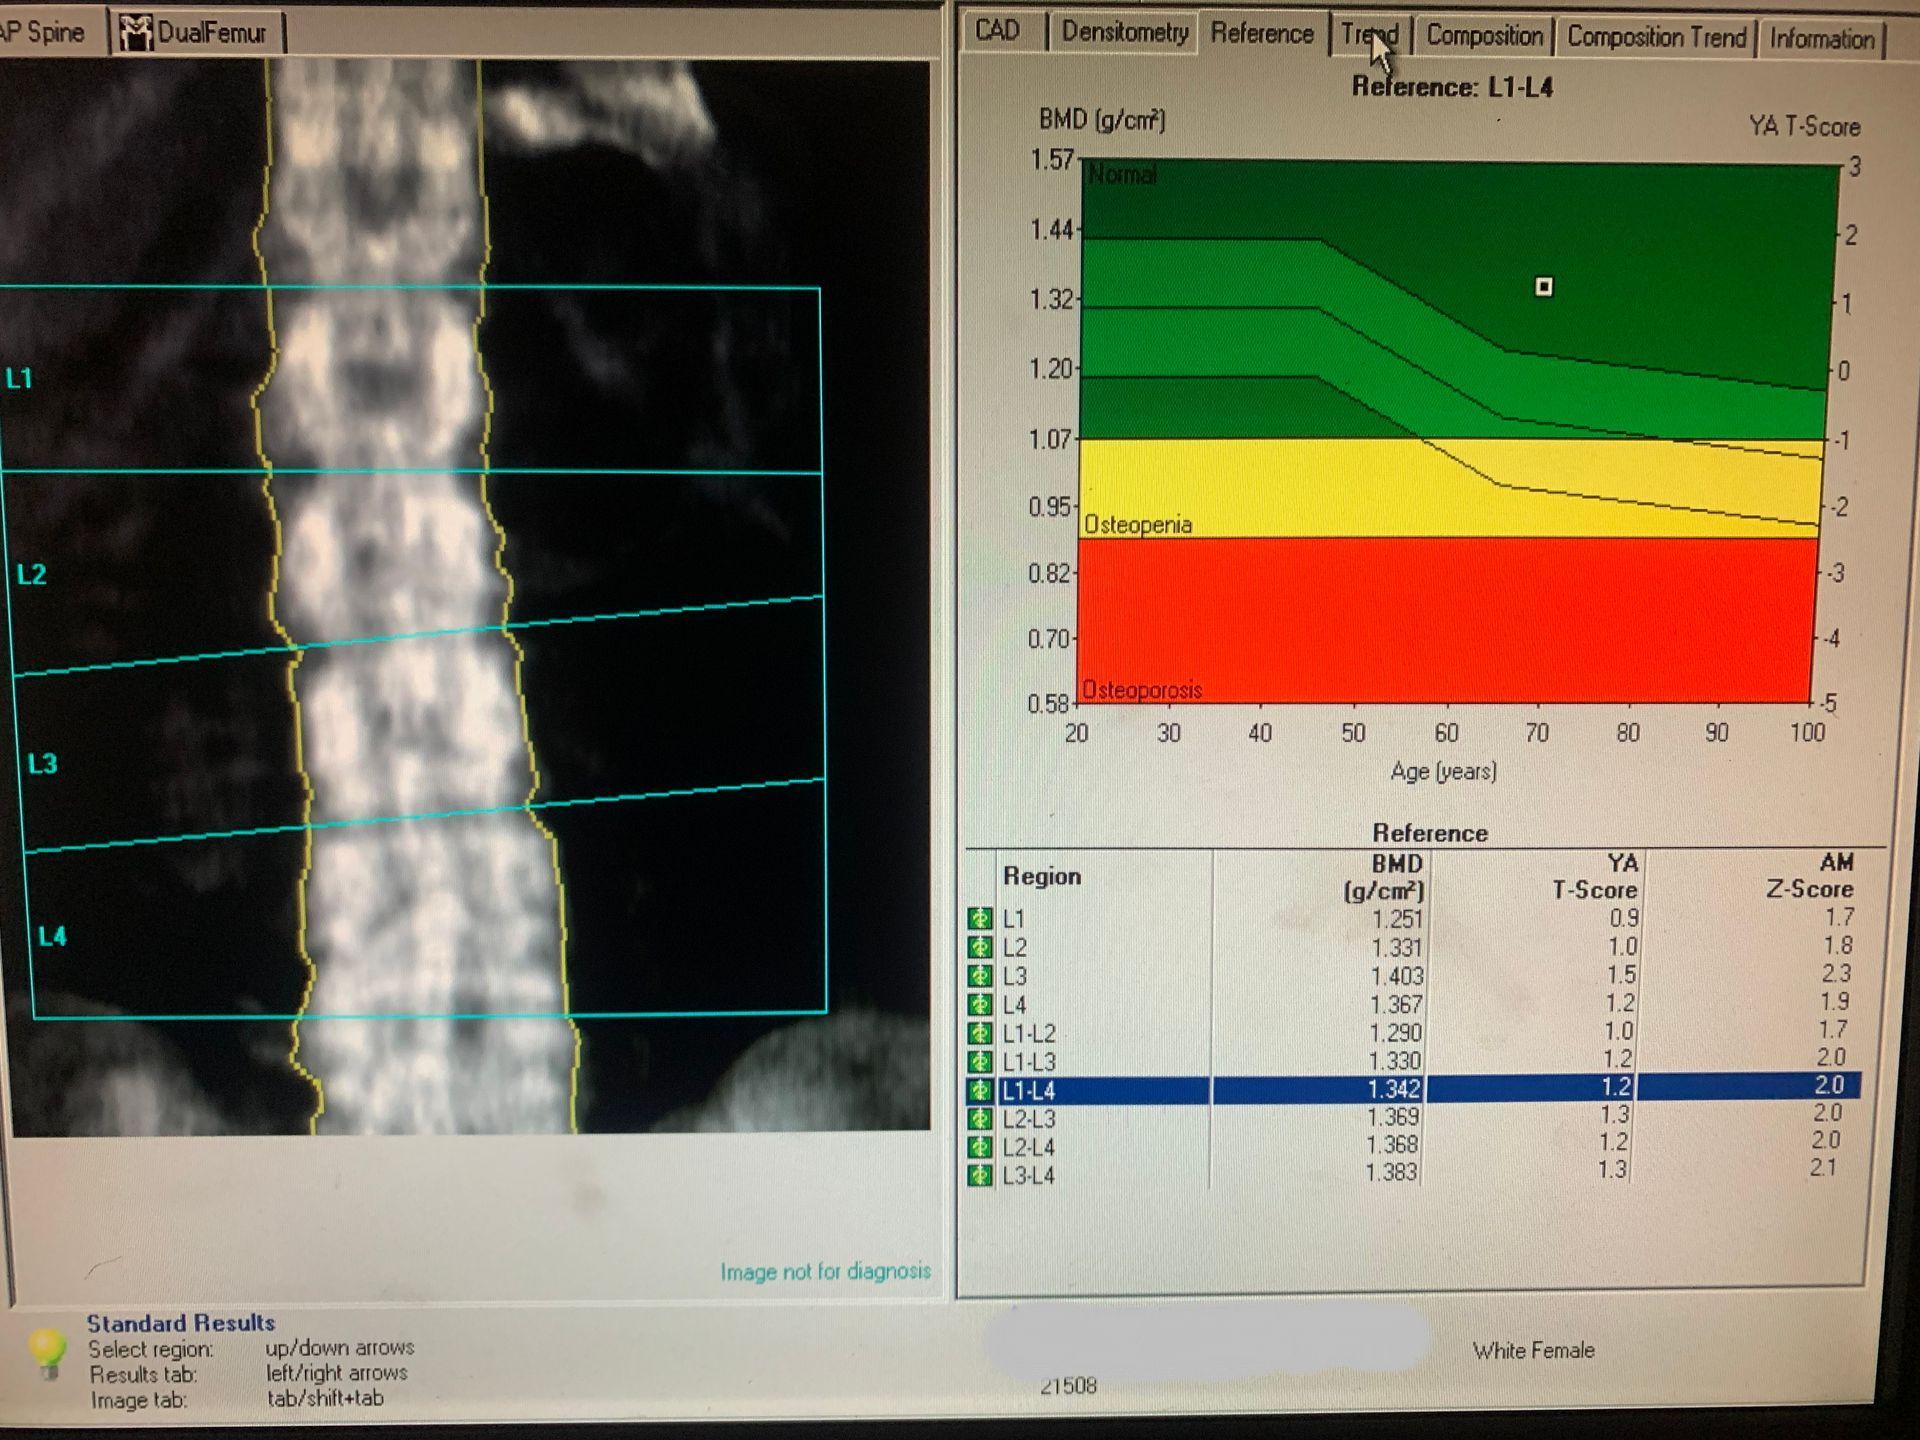

A DEXA Scan (Dual Energy X-ray Absorption) measures bone density, which is directly related to bone strength and helps doctors to predict the potential for osteoporosis and fracture. A DEXA scan uses an extremely low dose of radiation, is a fast and painless exam, and is considered safe for use on patients of any age. Generally speaking, women over 50 should get a DEXA scan once every two years, although it is helpful for those in their early 40s. to compare with future years.

A DEXA Scan (Dual Energy X-ray Absorption) measures bone density, which is directly related to bone strength and helps doctors to predict the potential for osteoporosis and fracture.A DEXA scan uses an extremely low dose of radiation, is a fast and painless exam, and is considered safe for use on patients of any age.

Generally speaking, women over 50 should get a DEXA scan once every two years, although it is helpful for those in their early 40s to have a baseline exam for comparison in the years to come.